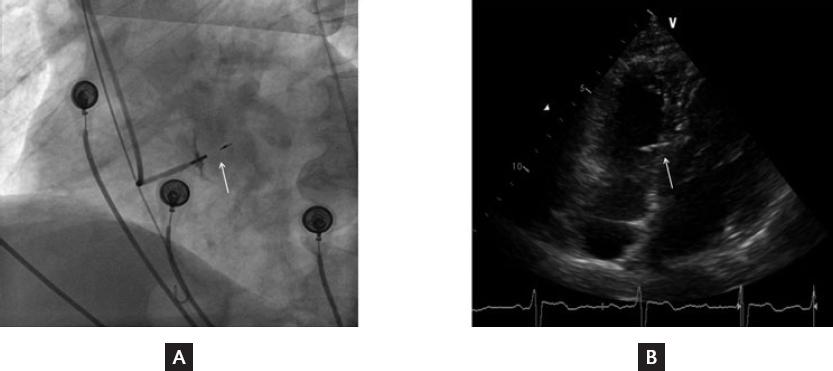

In total, 138 patients who underwent attempted LBBAP for symptomatic bradycardia were enrolled in this study. Finally, LBBAP was successfully achieved in 126 patients; in the remaining 12 patients, it failed and left ventricular septum pacing was chosen. Clinical characteristics of patients with LBBAP are summarized in table 1. The indications of pacemaker implantation were sinus node dysfunction in 70 patients (56%), atrioventricular block in 48 patients (38.4%), and atrial fibrillation with long RR interval in 7 patients (5.6%). Figure 1 shows the position of 3830 leads in the interventricular septum in successful LBBAP by X-ray and echocardiogram. Figure 2 shows the developing process of pacing ECG during LBBAP and the fluoroscopic images of sheath angiography and final stage.

Figure 1 Position of the 3830 lead in the interventricular septum. A, Final fluoroscopic image of the 3830 lead. B, Final echocardiogram image of the 3830 lead. The white arrows refer to the head part of 3830 lead stuck in the interventricular septum.